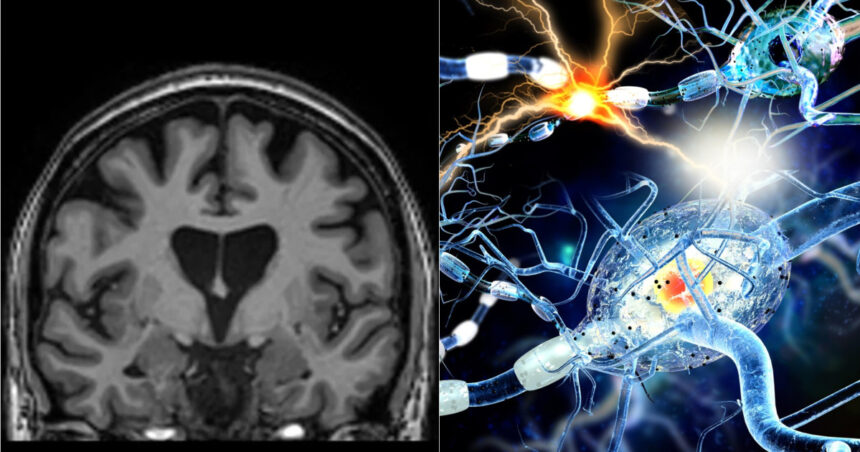

Noul tratament, testat de UniQure, implică utilizarea unui tip de material genetic, micro-ARN, care oprește producerea proteinei toxice. Procedura necesită o intervenție chirurgicală delicată de 12 până la 18 ore, în care un virus inofensiv, modificat genetic, este introdus în creier. Acest virus acționează ca un „poștaș microscopic”, livrând o secvență de ADN în neuronii pacienților, care devin astfel capabili să producă terapia. Molecula micro-ARN (AMT-130) rezultat din acest proces are rolul de a intercepta și dezactiva instrucțiunile celulelor pentru producerea proteinei huntingtin.